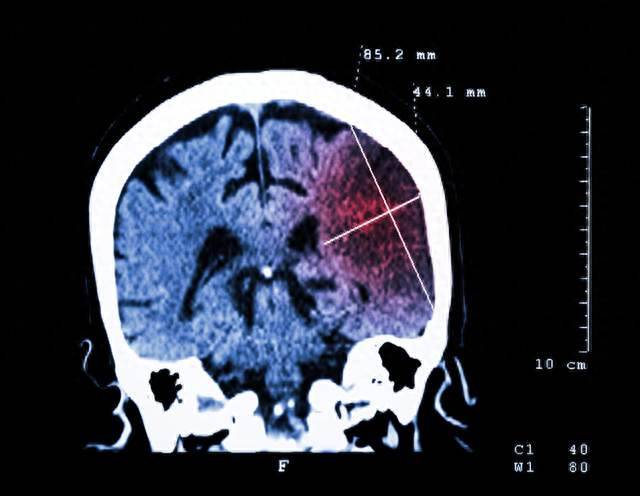

頸動脈斑塊,指的是人體脖頸兩側負責腦供血的動脈,因雜質積累出現動脈硬膜病變,發展為動脈壁炎癥、增厚、硬化,最后形成斑塊。

2020年,醫學權威刊物《柳葉刀》子刊發表了一項由北京大學、哈佛大學、帝國理工大學共同完成的研究。該研究評估了全球21個國家和地區的頸動脈粥樣硬化的病發率、患病人數、危險因素,最終證實:2020年,全球頸動脈粥樣硬化患者接近20億,其中中國占2.7億,頸動脈斑塊患者2億人。

頸動脈因斑塊而狹窄、堵塞,一旦斑塊脫落,就會形成血栓。頸動脈斑塊如果進入大腦,會造成